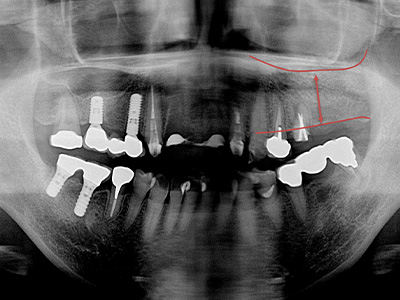

ソケットリフト

(クレスタルアプローチ)上顎の骨が足りない場合に行う治療法です。インプラントを埋める穴から、上顎洞の底を押し上げて骨補填材を入れ、骨の厚みを増やします。傷口は小さく、治癒まで約4〜6ヶ月かかります。